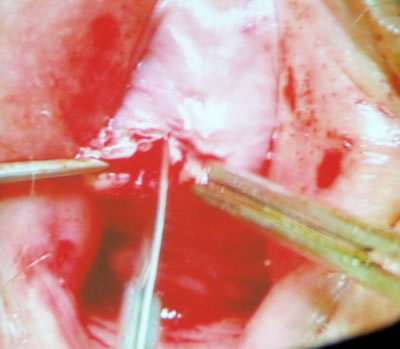

Далее Олег Борисович провел специальным проводником синтетическую

полипропиленовую петлю через отмеченные на коже места. Петля

прошла снаружи внутрь через запирательное отверстие. Пальцем,

введенным в разрез у уретры оператор контролировал прохождение

кончика проводника. Когда инструмент оказался в ране, профессор

провел с помощью его конец петли. Тоже он проделал с другой

стороны. Оператор отрегулировал минимальное натяжение петли,

срезал избытки ее концов. Раны ушил.